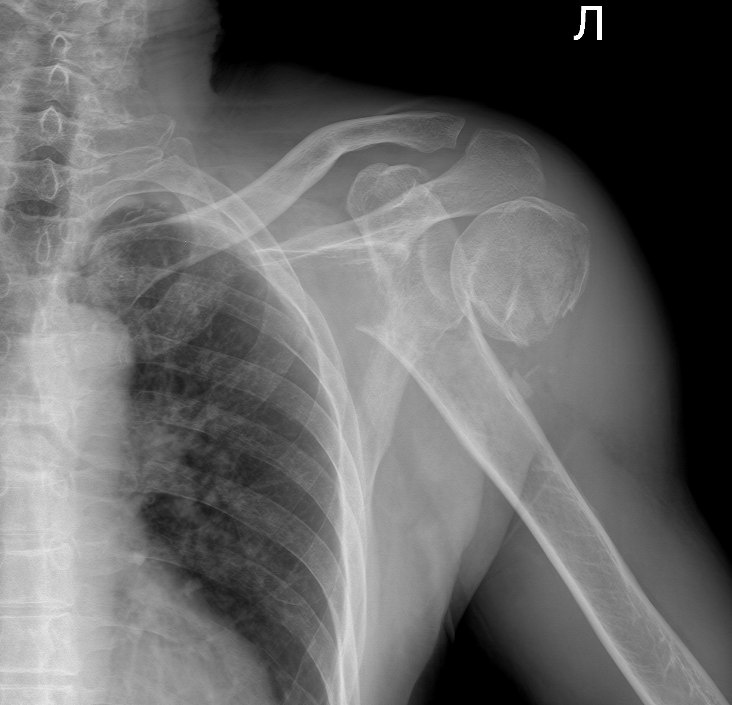

Перелом хирургической шейки плеча с выраженным смещением костных отломков. Пациента ждёт операция и длительное восстановление.